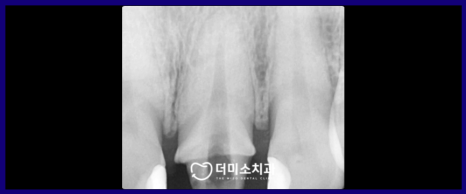

정밀한 검사를 위해

파노라마 사진과 X-ray 사진을

촬영해 보았더니

신경치료 후 채워 넣는 치과 재료가

뿌리 끝까지 꼼꼼하게 채워지지 않은

불완전 근관치료 상태인 것을

확인할 수 있었는데요.

이 경우 재신경치료가

필요한 상황이었습니다.